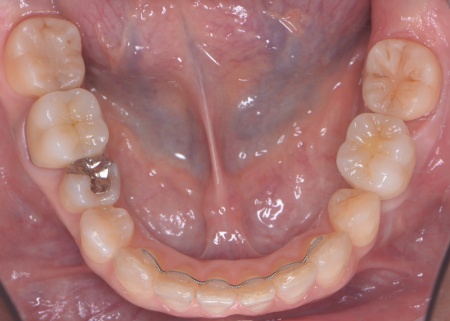

50代女性 インプラント・矯正・被せ物治療で見た目と噛み合わせを改善した症例

「以前治療した左下奥歯が思うように噛めない。また、矯正治療を受けた前歯でうまく噛めない」とご相談いただきました。

拝見したところ、左下奥歯(第1大臼歯)は以前、歯根分割処置が行われていました。

しかし残していた歯根の状態も悪化しており、治療しても温存は困難と判断しました。

さらに患者様は全体的に歯並びや噛み合わせに問題があり、特に上下の前歯は噛んだ際に隙間ができ食べ物を噛み切りにくい状態です。

また、右の上下奥歯2本に装着されている白い被せ物や銀歯が劣化により歯に合わなくなり、虫歯の再発リスクが高まっていました。

以上のことから、噛み合わせを改善する総合的な治療が必要と診断しました。

②①と並行して上下歯列にワイヤー矯正のマルチブラケット装置を装着し、歯並びと噛み合わせを整える。

③矯正治療と並行して左下奥歯を抜歯し、インプラント治療を行う。

インプラントを支えるための骨の量が十分でないため、人工材料を用いて骨を再生させる骨造成(GBR)を併用しながらインプラントを埋入する。

インプラントがしっかりと骨に定着したことを確認してから、人工歯を取り付ける。

④矯正終了後に右上下奥歯の合わなくなった被せ物を除去し、自然な白さで強度もあるジルコニアセラミッククラウンを装着する。